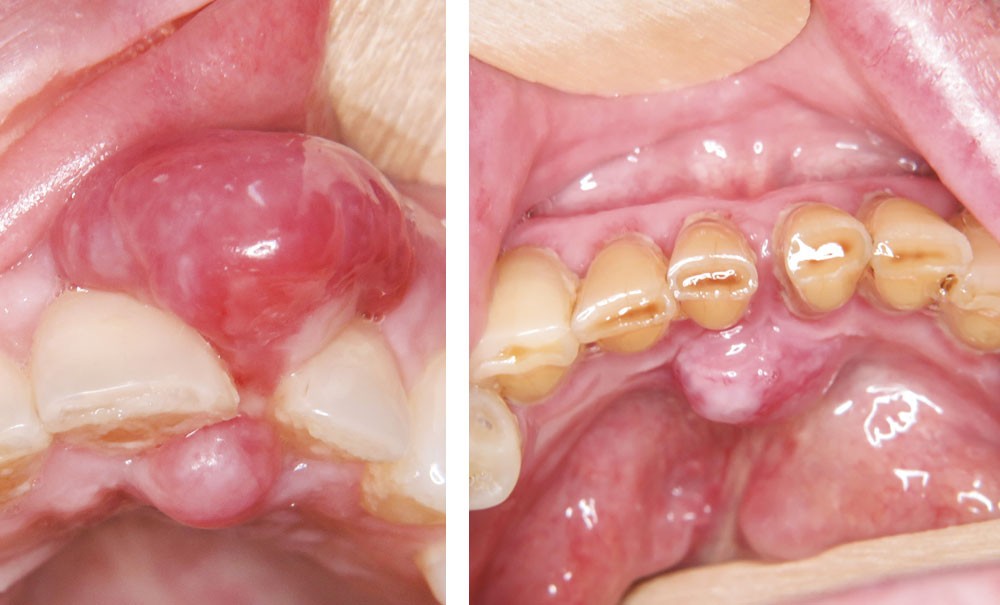

On observait un nodule gingival en bissac d’environ 1,5 cm de diamètre développé entre 21 et 22. Le nodule avait un aspect érythémateux violine et était par place ulcéré. La palpation révélait une lésion de consistance ferme. Le sondage objectivait une poche de 10 mm en vestibulaire de 22.